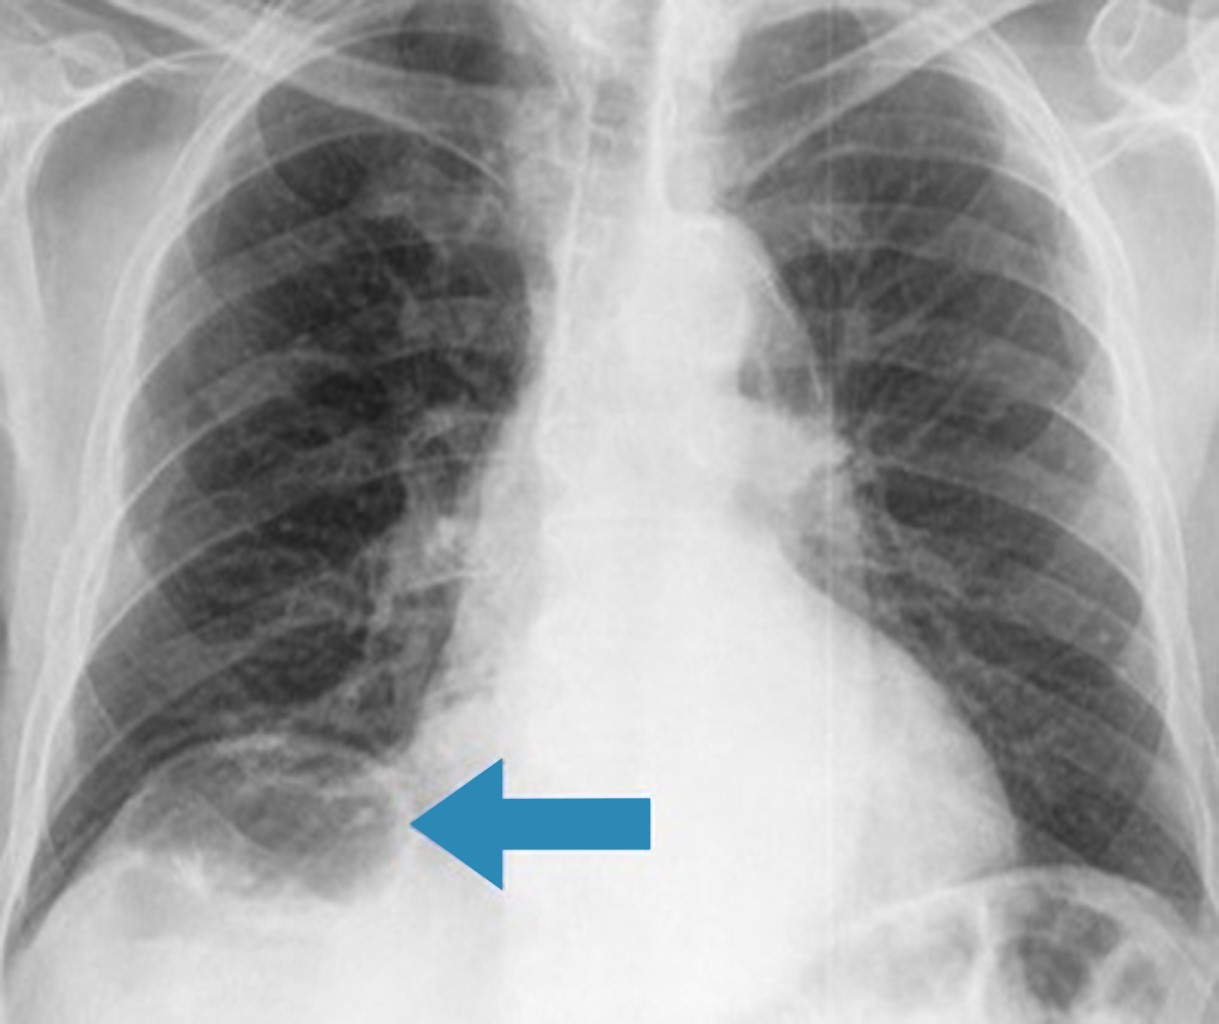

Hombre de 84 años con antecedentes de hipertensión arterial sistémica e hiperplasia prostática benigna. Fue visto en la consulta de medicina interna para realización de valoración preoperatoria para resección transuretral de próstata, observándose de manera incidental la presencia de gas subdiafragmático derecho (Figura 1). Se refirió asintomático. En tomografía abdominal se confirmó la interposición hepatodiafragmática del ángulo hepático del colon (Figura 2), lo que definió la presencia de signo de Chilaiditi.

Figura 1